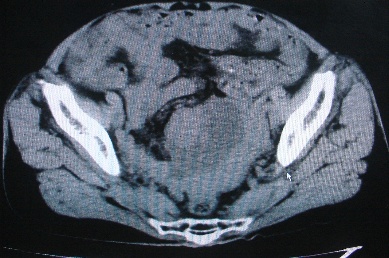

以下是引用卜一在2007-4-30 15:29:00的发言:[br]子宫明显增大,不规则,子宫壁不规则增厚,子宫腔明显缩小,子宫右侧软组织团块与子宫关系密切,内见低密度坏死区。考虑:子宫癌并周围侵润。